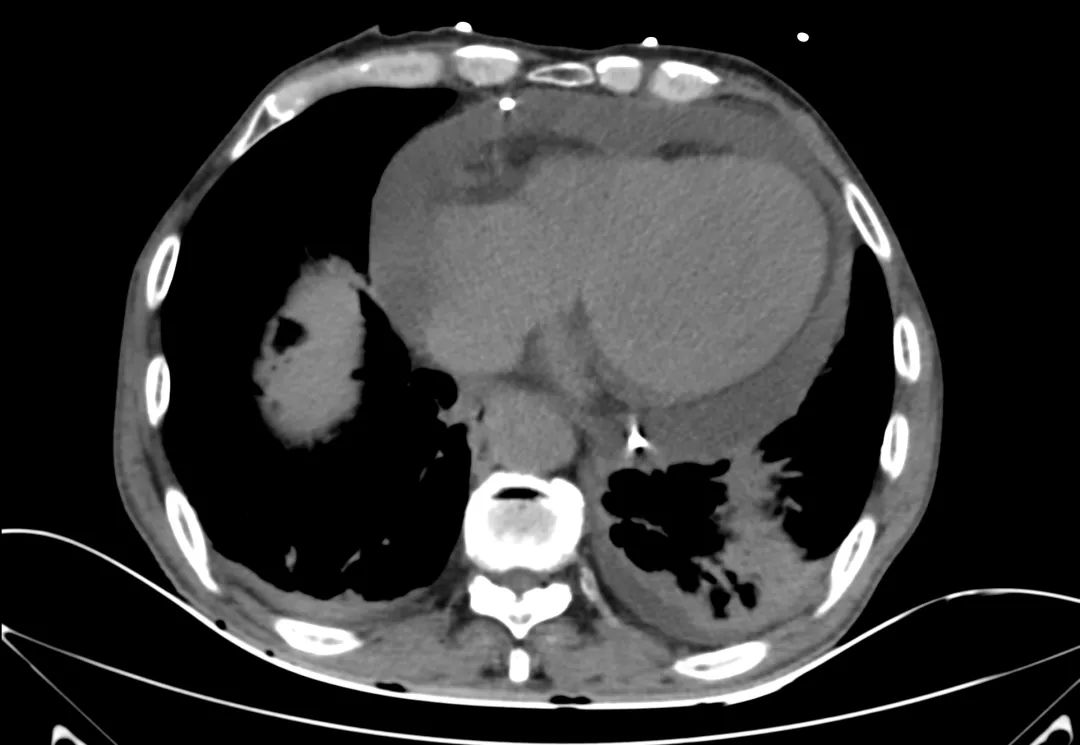

胸部CT

主动脉根部CT断层

根部角度/瓣环/左室流出道

瓣上结构2,4,6,8,10,12mm

SOV/STJ/AAO

左冠风险评估